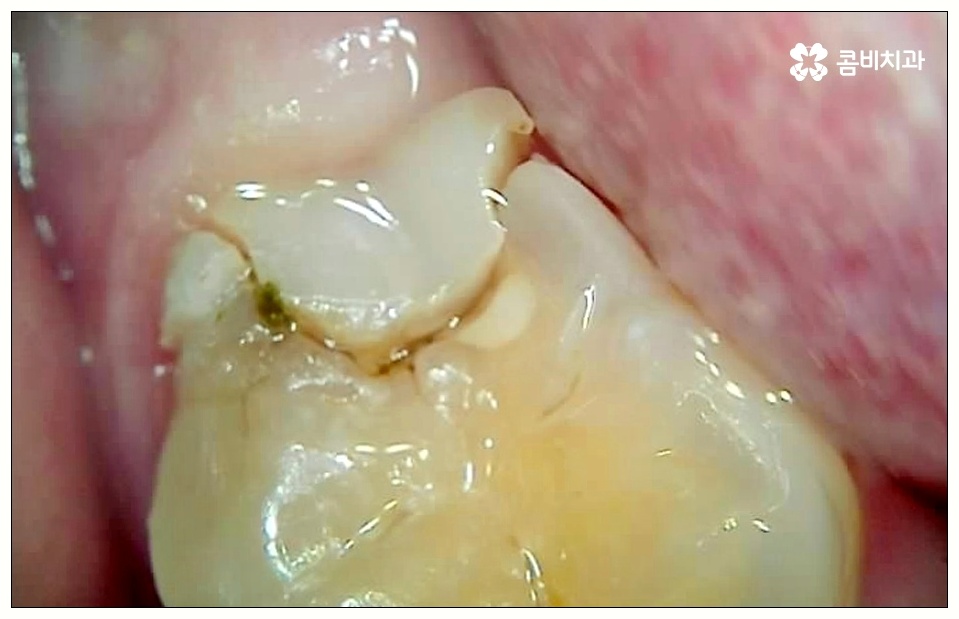

하지만 꼭 발치 처치를 받아야 하는 사랑니도 있는데 그 중 대표적인 것이 바로 어금니 사이 충치 를 유발한 경우로, 비스듬하게 나온 사랑니가 앞의 어금니를 밀면서 압박을 주고 옆면에 충치를 일으키는 등 손상시키고 있다면 늦기 전에 발치 처치를 받으실 필요가 있습니다.

위생 관리가 제대로 되지 않으면 치태와 치석이 늘어나 세균이 증식하면서 구취는 물론 충치가 유발되게 되는데, 이것을 방치할 경우 사랑니 자체가 썩어 옆의 어금니로 충치가 옮겨가게 되거나 사랑니와 어금니 사이 충치 발생으로 인해 어금니까지 덧씌워야 하는 상황이 올 수도 있으니 주의하실 필요가 있어요.

특히 어금니 사이 충치 는 눈에 잘 보이지 않을 뿐만 아니라 어느 정도 진행이 될 때까지 통증이 크지 않기 때문에 치료시기를 놓치게 되는 경우가 많이 있는데요.

이렇게 병증이 깊어지게 되면 치은에도 쉽게 손상이 일어나고 치아 내부 밀도가 떨어져 치아 파절이 일어날 수 있으며 결국 사랑니만 뽑는 것이 아니라 저작 기능에 중요한 역할을 하는 어금니까지 발치해야 하는 상황이 생길 수도 있기 때문에 초기에 잘 대처하실 필요가 있어요.

치아 사이 충치는 법랑질이 두꺼운 교합면, 즉 음식을 잘게 부수는 윗면이 아니라 치아와 치아 사이에 맞닿고 있어 비교적 법랑질의 두께가 얇고 신경까지의 거리가 짧은 옆면에 생기는 것이기 때문에 병증이 진행되는 속도가 빠르고 치료하기가 까다로워 될 수 있는대로 빨리 대처하실 필요가 있어요.

사랑니로 인해 어금니 사이 충치 가 발생하고 치아 파절이 일어나 신경까지 손상이 일어난 경우 원인이 된 사랑니를 발치한 후에 신경 치료와 크라운 처치를 통해 어금니 수복을 해 주게 되는데 이 때 근관 소독 및 밀봉 후 통증이 없어졌다고 해서 크라운 처치를 해 주지 않은 채로 치료를 마치게 되면 2차 감염이 일어나거나 외부 충격으로 인해 또 다시 파절이 생길 가능성이 높아 어렵게 살린 어금니를 잃게 될 수도 있으니 꼭 남아 있는 치아를 전체적으로 덮어주는 크라운 처치를 통해서 보호해 주시는 것을 권유드리고 있습니다.